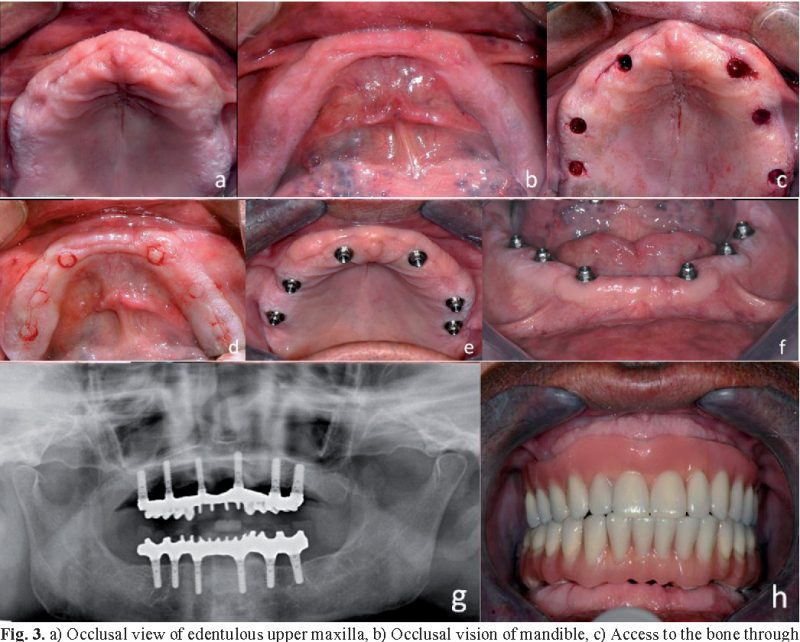

Bệnh nhân được chẩn đoán qua phim CT trước phẫu thuật đặt implant

Cấy ghép implant thay thế toàn bộ các răng

Nếu toàn bộ các răng trên một hàm bị mất, giải pháp cổ điển thường là làm một phục hình toàn hàm. Nay nhờ có phương pháp cấy ghép implant, toàn bộ hàm răng giả được cố định vào hàm, tạo sự vững chắc ổn định và ngăn ngừa tình trạng tiêu xương so với dùng hàm giả tháo lắp.